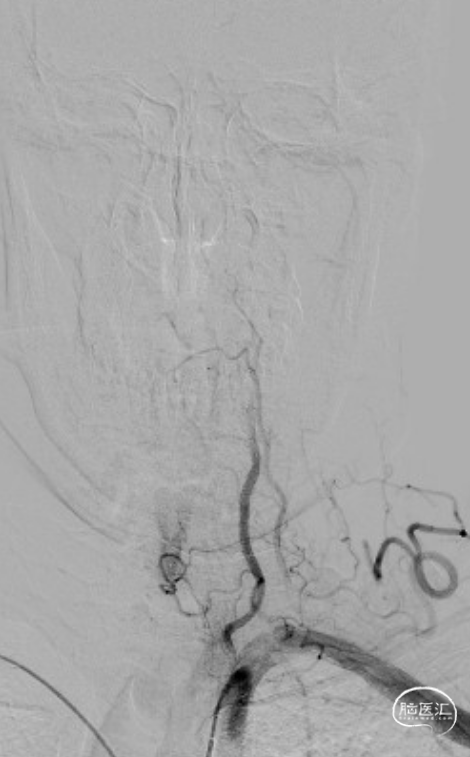

LSCA造影:LVA V2段闭塞。

RVA造影:RVA V4段重度狭窄。